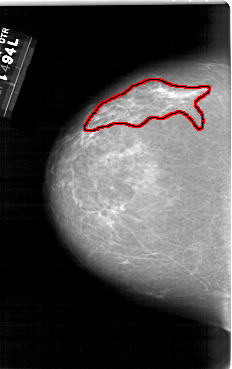

A_1186_1.LEFT_MLO

FILE: A_1186_1.LEFT_MLO.OVERLAY

TOTAL_ABNORMALITIES 1

ABNORMALITY 1

LESION_TYPE CALCIFICATION TYPE FINE_LINEAR_BRANCHING DISTRIBUTION SEGMENTAL

ASSESSMENT 5

SUBTLETY 1

PATHOLOGY MALIGNANT

TOTAL_OUTLINES 1

BOUNDARY